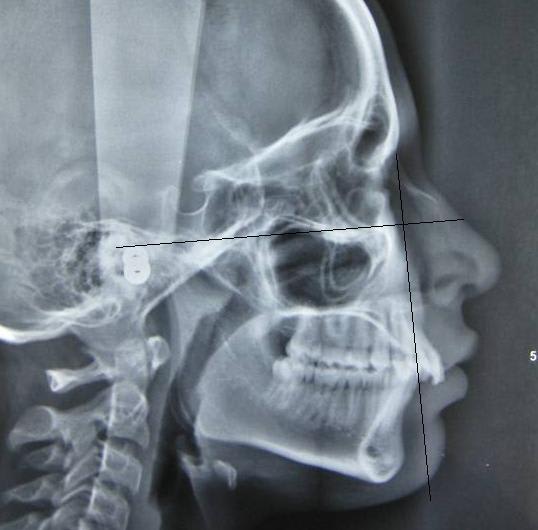

J'ai une patiente de 14 ans qui présente une full classe II due à un maxillaire en proposition car sur une base du crâne trop longue en antérieur. Le maxillaire a une longueur normale.

Voici les photos, radios et moulages du cas

Le maxillaire n'est pas si avancé que cela, par rapport a mac namara ( mais c'est normale, si c'est la base du crane qui est augmenté ) : donc : chirurgie pour raccourcir la base du crane ?

Sinon, extraction 14 24, c'est quand même moins lourd qu'un Lefort.